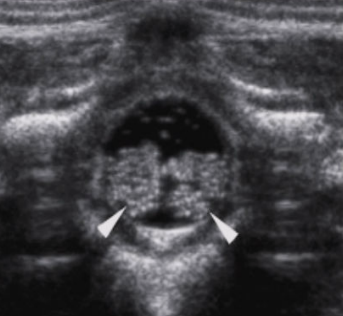

arrowheads

echogenic dura

*

echogenic vertebral arches

p

spinous process